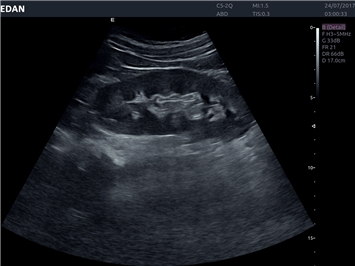

EDAN Acclarix LX4

Расширьте свои представления. Использование усовершенствованной платформой Acclarix система LX4 обеспечивает непревзойденную четкость изображений и интеллектуальный рабочий процесс для всех пользователей, являясь при этом наиболее экономичным решением.

EDAN Acclarix LX4 представляет собой инновационную ультразвуковую систему, построенную на усовершенствованной платформе Acclarix. Сочетание высокого качества визуализации с интеллектуальным рабочим процессом делает эту систему оптимальным выбором для клиник, ценящих эффективность и экономичность.

• 3D/4D-визуализация с автоматическим редактированием объема (eFace)

• Автоматизированные измерения в акушерстве

• Акушерства и гинекологии